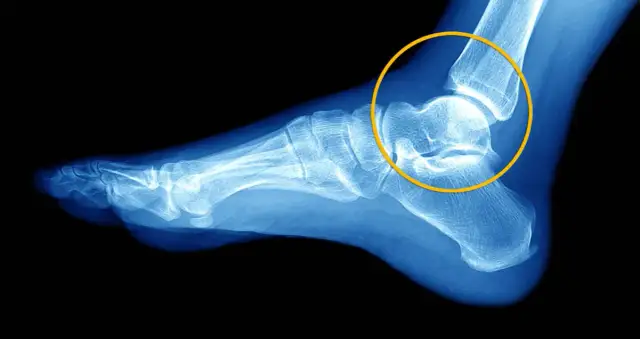

Opuchlizna po skręceniu kostki? Sprawdź, ile trwa obrzęk zależnie od stopnia urazu. Odkryj protokół POLICE, domowe sposoby i czerwone flagi. Szybko wróć do formy!

Skręcenie stawu? Zrozum objawy, stopnie urazu i protokół PRICE. Dowiedz się, kiedy iść do lekarza oraz jak skutecznie leczyć i zapobiegać nawrotom!